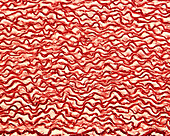

13613450 - Elastic lamellae in aorta, light micrograph

13613436 - Elastic lamellae in aorta, light micrograph

13613447 - Elastic lamellae in aorta, light micrograph

13613449 - Elastic lamellae in aorta, light micrograph

13613433 - Elastic lamellae in human aorta, light micrograph